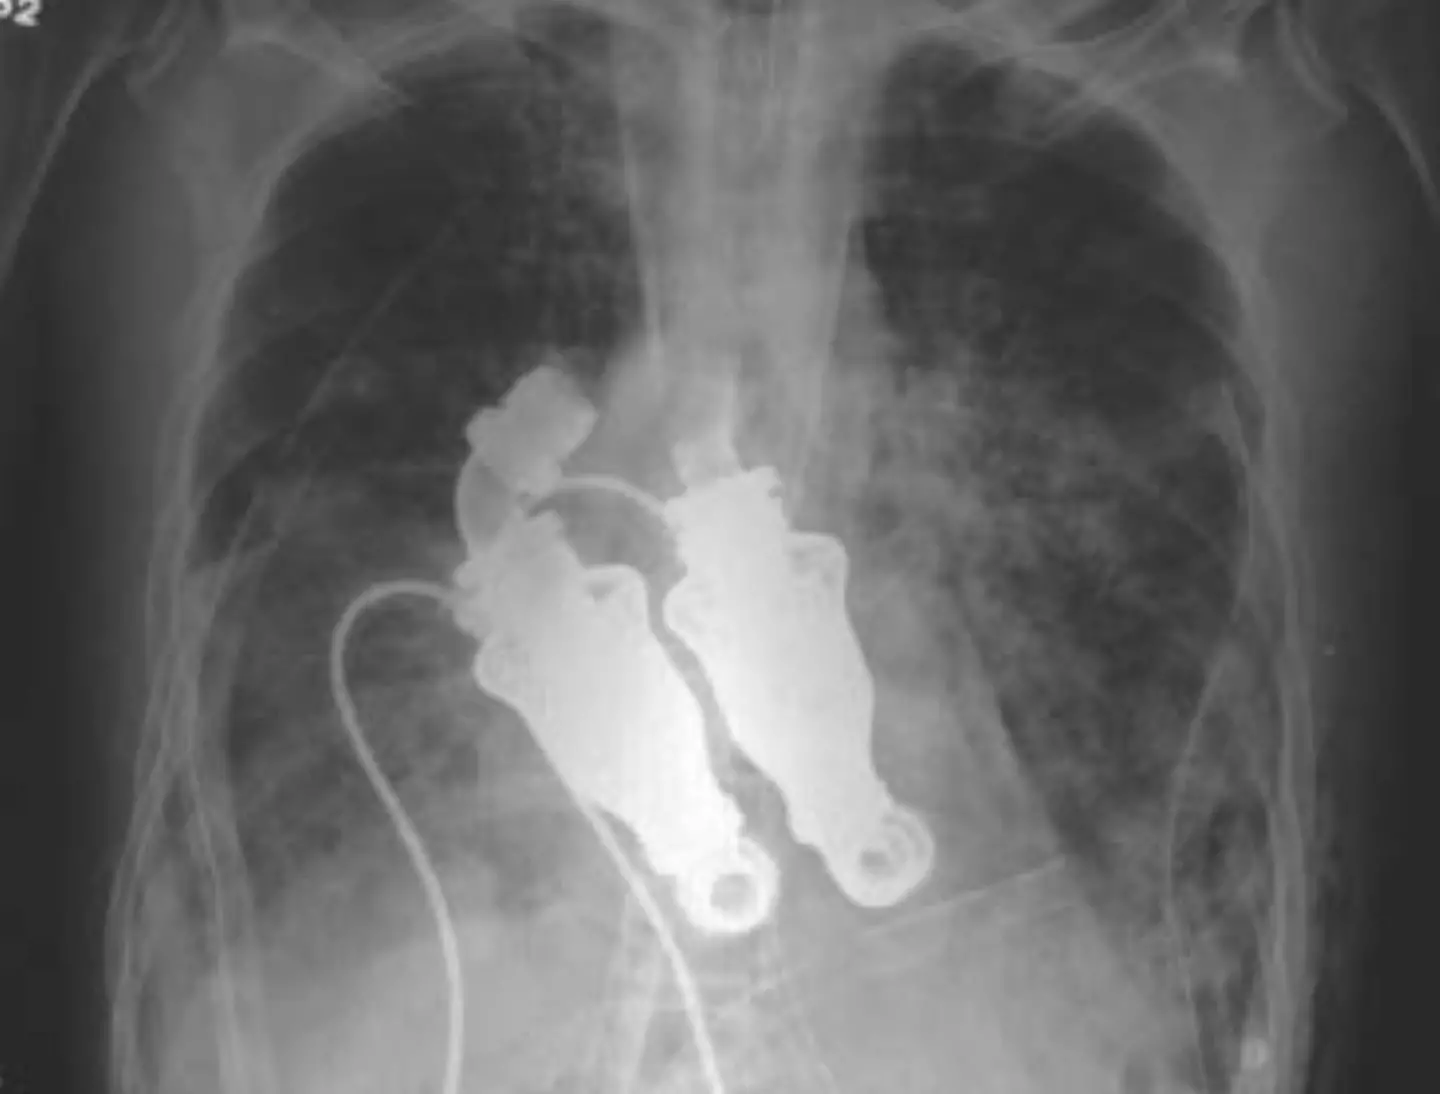

After decades of trial and error among surgeons desperately trying to create a machine that wouldn’t break down or cause blood clots and infections, two doctors at the Texas Heart Institute developed a device that used whirling rotors to pump blood around the body without a heartbeat.

Dr Billy Cohn and Dr Buz Frazier first tested the idea in an eight-month-old calf called Abigail, removing her heart and successfully replacing it with two centrifugal pumps, which circulated the blood through her.

After practicing on 38 calves, Cohn and Frazier progressed to human trials – selecting a 55-year-old man called Craig Lewis, who was suffering from amyloidosis, a rare autoimmune disease that causes a build-up of abnormal proteins and, in turn, rapid heart, kidney and liver failure.

In March 2011, she approached Cohn and Frazier, who removed her husband’s heart and installed the artificial device

She said her husband – who worked for the city of Houston, maintaining the city’s vast system of wastewater pumps – would have appreciated the pulseless heart cobbled together from various materials, with Cohn explaining: "Dacron on the inside and fiberglass impregnated in silicone on the outside.

"There's a moderate amount of homemade stuff on here."

The doctors said the continuous-flow pump should last longer than other artificial hearts, and would cause fewer problems.